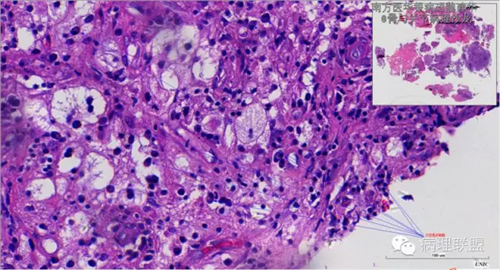

来源于组织细胞的相似性骨病ECD vs RDD 看图说话